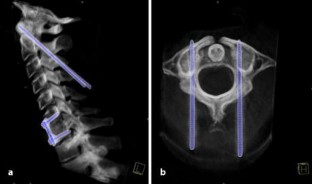

Die 25-jährige Patientin erlitt nach Verkehrsunfall eine dislozierte Jefferson-Fraktur, eine Densfraktur vom Typ II nach Anderson und d’Alonso mit Protrusion in das Foramen magnum sowie eine HWK-6/7-Luxationsfraktur. Es erfolgte die ventrale Spondylodese C6/7 mittels Beckenkammspan und H-Plattenfixation, sowie die dorsale temporäre Spondylodese mittels Kirschner-Drähten nach Magerl C1/2 und die zusätzliche Halotransfixation, wobei so der Denshochstand beseitigt werden konnte. Die Aufhebung der temporären Transfixation C1/2 durch Entfernung der Kirschner-Drähte sowie die Entfernung des Halofixateursystems fand nach 11 Wochen statt.

The 25 year old patient was involved in a motor vehicle accident that resulted in a dislocated Jefferson’s fracture, an odontoid fracture type II (Anderson and d’Alonso) with protrusion into the foramen magnum, and a dislocated C 6/7 fracture. A ventral spondylodesis C6/7 was followed by temporary dorsal spondylodesis C1/2 with k-wires (Magerl) and additional halo vest immobilisition after closed reduction. The temporary percutaneous fixation C1/2 was removed after 11 weeks, as was the halo vest immobilisition.

Abb. 1a

Abb. 2a